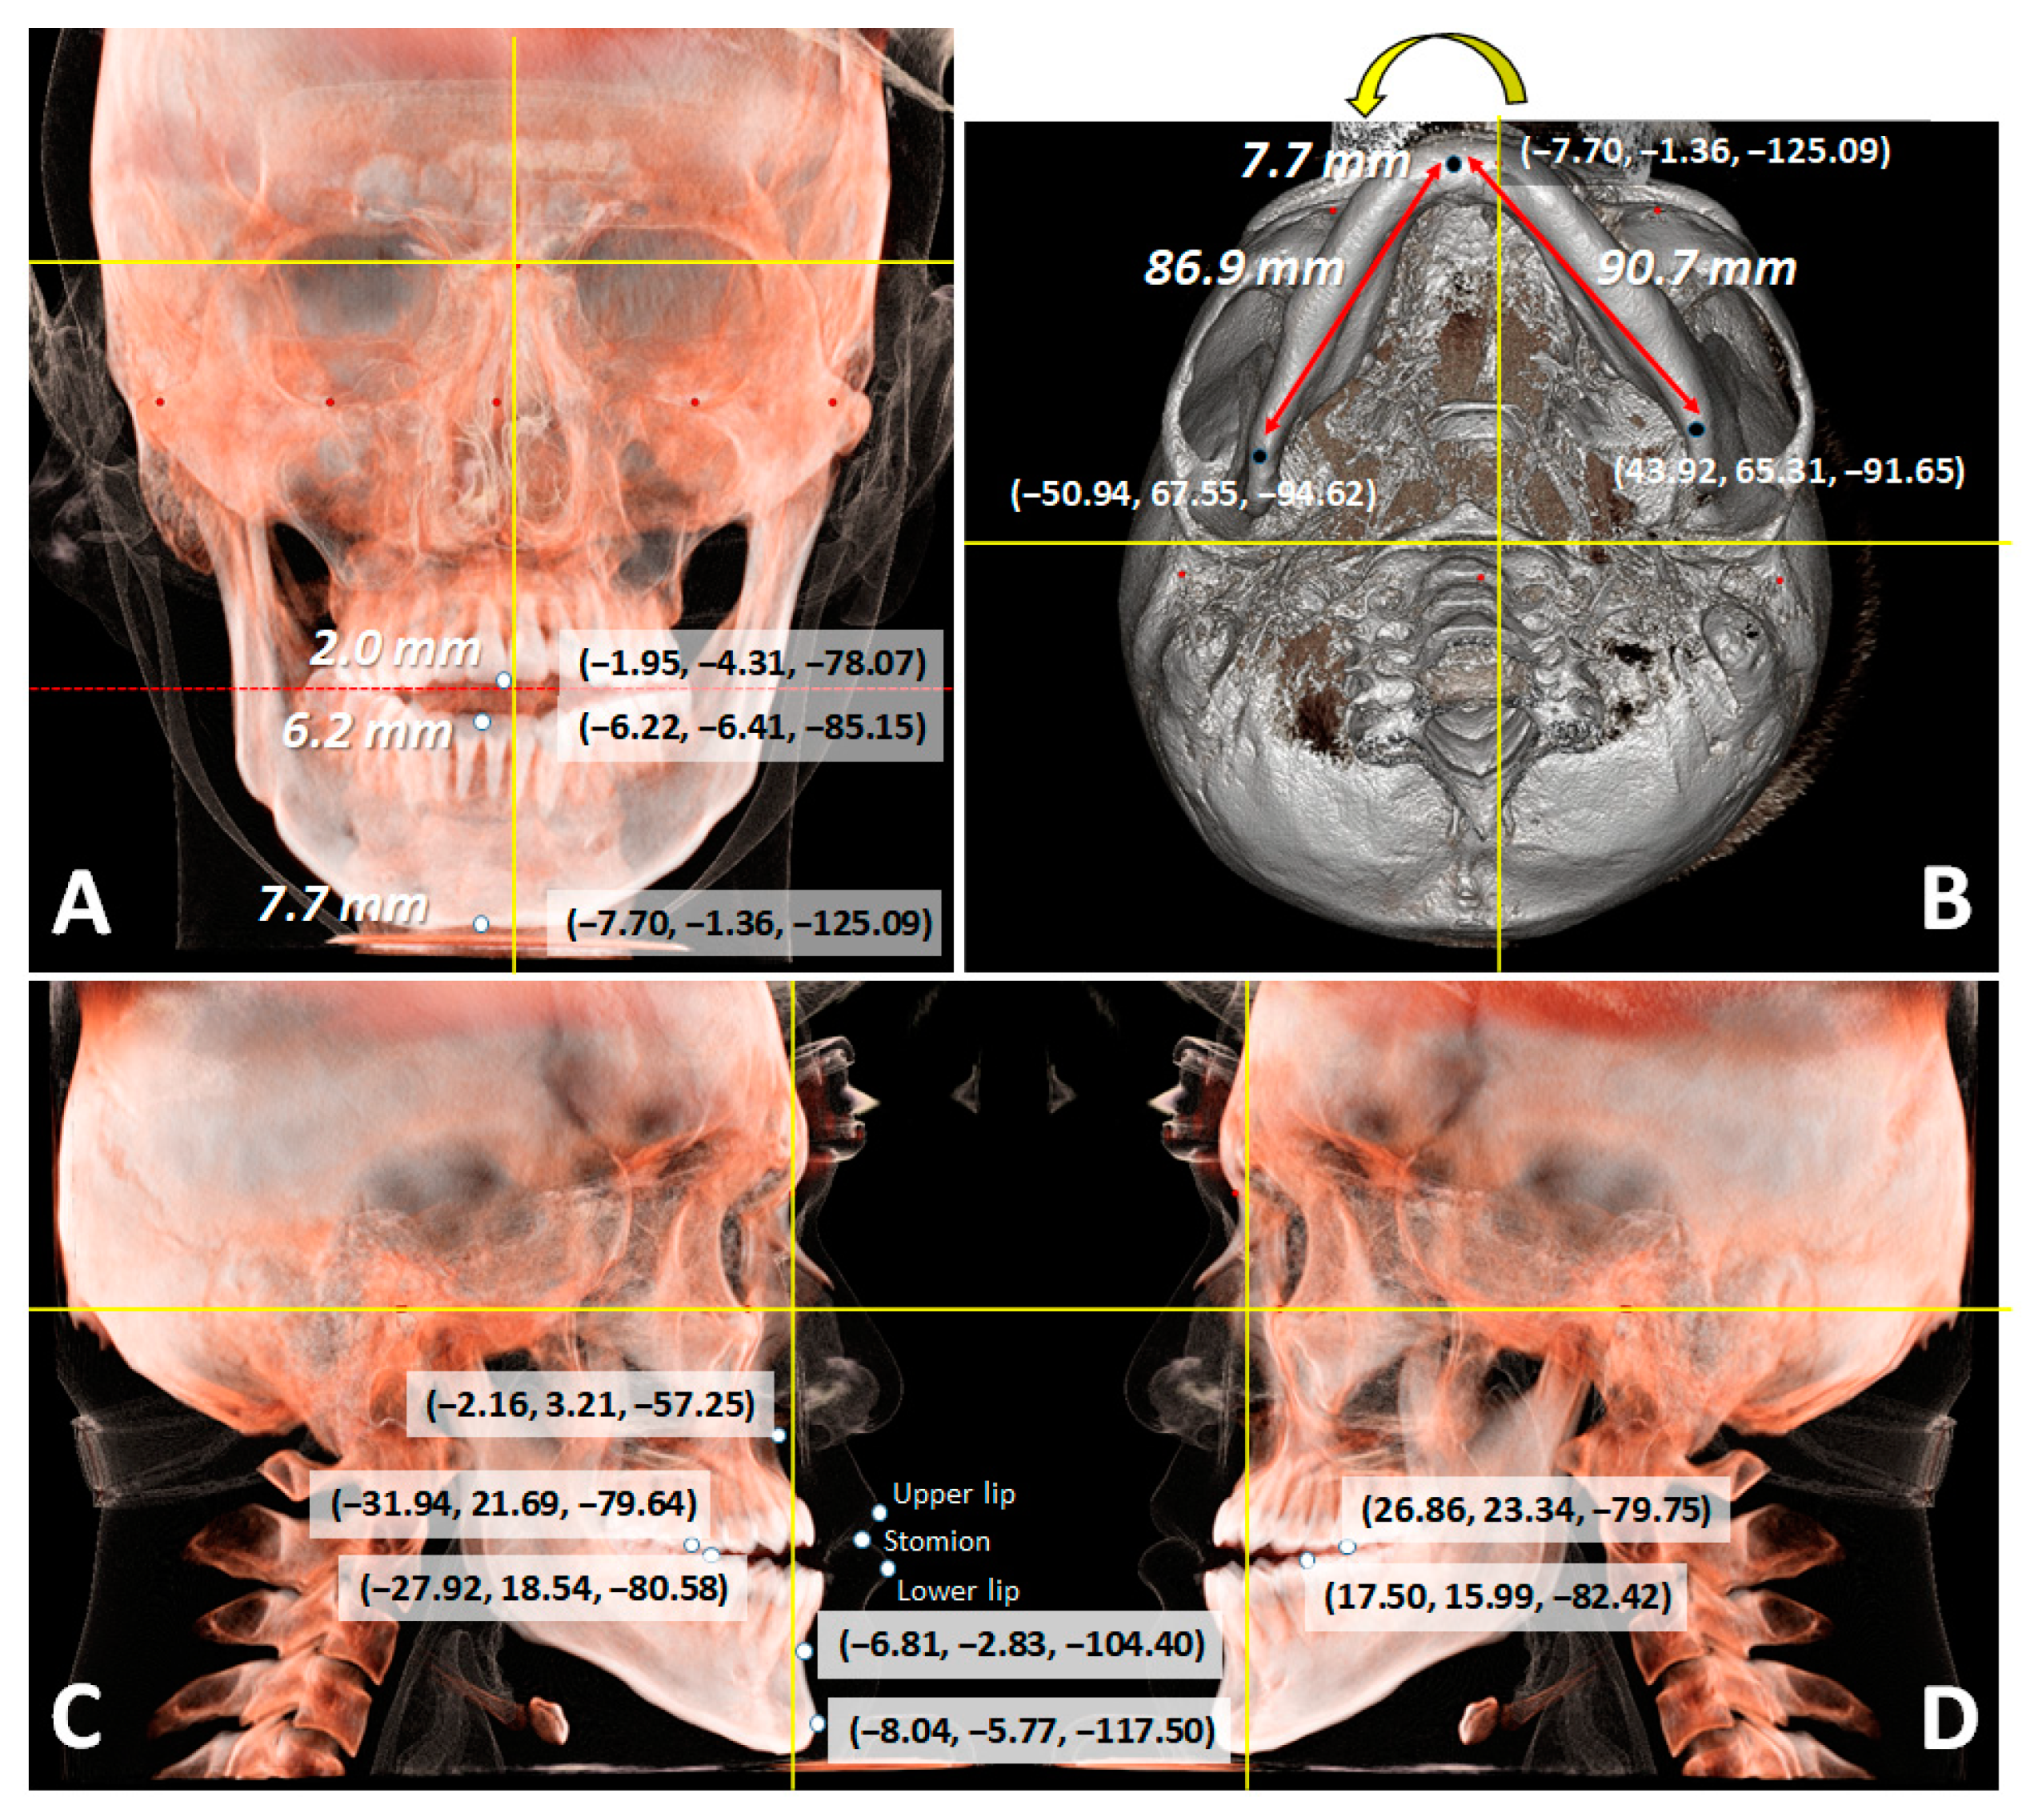

2.1. Diagnosis and Etiology

| Variables | T1 (x, y, z) | T3 (x, y, z) |

|---|---|---|

| U1MP | (−1.95, −4.31, −78.07) | (−2.04, −3.66, −81.29) |

| L1MP | (−6.22, −6.41, −85.15) | (−1.82, −0.90, −79.89) |

| RU6CP (right) | (−31.94, 21.69, −79.64) | (−31.43, 22.41, −80.25) |

| LU6CP (left) | (26.86, 23.34, −79.75) | (25.86, 23.42, −81.27) |

| RL6CP (right) | (−27.92, 18.54, −80.58) | (−28.35, 20.14, −79.59) |

| LL6CP (left) | (17.50, 15.99, −82.42) | (22.63, 21.56, −79.98) |

| Point A | (−2.16, 3.21, −57.25) | (−1.03, 3.25, −58.82) |

| Point B | (−6.81, −2.83, −104.40) | (−4.98, −1.87, −103.55) |

| Pogonion | (−8.04, −5.77, −117.50) | (−6.13, −5.20, −119.91) |

| Menton | (−7.70, −1.36, −125.09) | (−5.46, 0.09, −126.68) |

| Gonion (right) | (−50.94, 67.55, −94.62) | (−49.93, 69.01, −94.76) |

| Gonion (left) | (43.92, 65.31, −91.65) | (44.47, 65.37, −93.14) |

| Stomion | (−2.69, −14.54, −77.29) | (−1.37, −14.40, −80.00) |

| UL | (−2.05, −19.23, −71.22) | (−0.84, −19.52, −72.61) |

| LL | (−3.41, −22.19, −84.05) | (−0.64, −20.06, −87.60) |